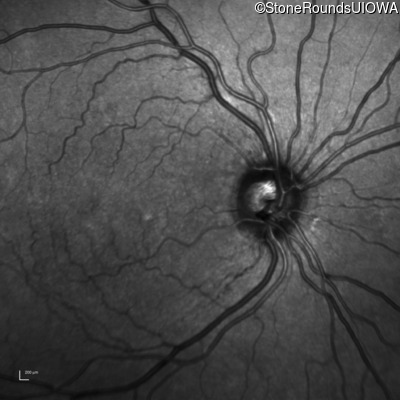

Infrared Fundus Photograph - Right - 20/400 sc

Exemplar